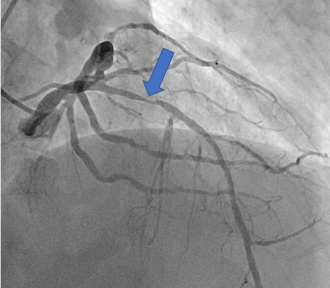

その後撮影した冠動脈造影。CTと同様、右冠動脈に高度狭窄を認める(矢印)。